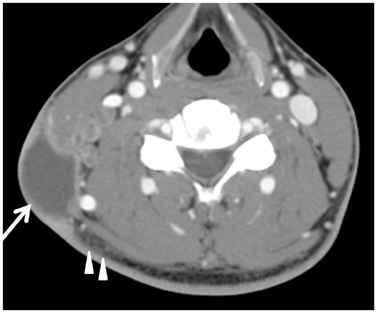

To compare the clinical and CT manifestations of Kikuchi disease (KD) and tuberculous lymphadenitis (TL).

KD patients showed a female predominance (67.1%). Patients with TL were older. Leukocytopenia and increased ESR were more frequent in patients with KD. KD more commonly affected lymph nodes in level II, III, and V, while TL more commonly involved lymph nodes in the upper paratracheal area. Perinodal fat infiltration was more frequent in KD. Muscle abscess was seen in patients with TL only (14%). Necrotic lymph nodes were more frequent in TL. A thin type was more frequent in TL.

KD showed female predominance, leukocytopenia, increased ESR, involvement of levels II, III, and V and frequent perinodal fat infiltration. TL patients were older than KD patients, were commonly affected in the upper paratracheal area, abscesses were shown only in this group and thin type necrotic lymph nodes were more frequent.